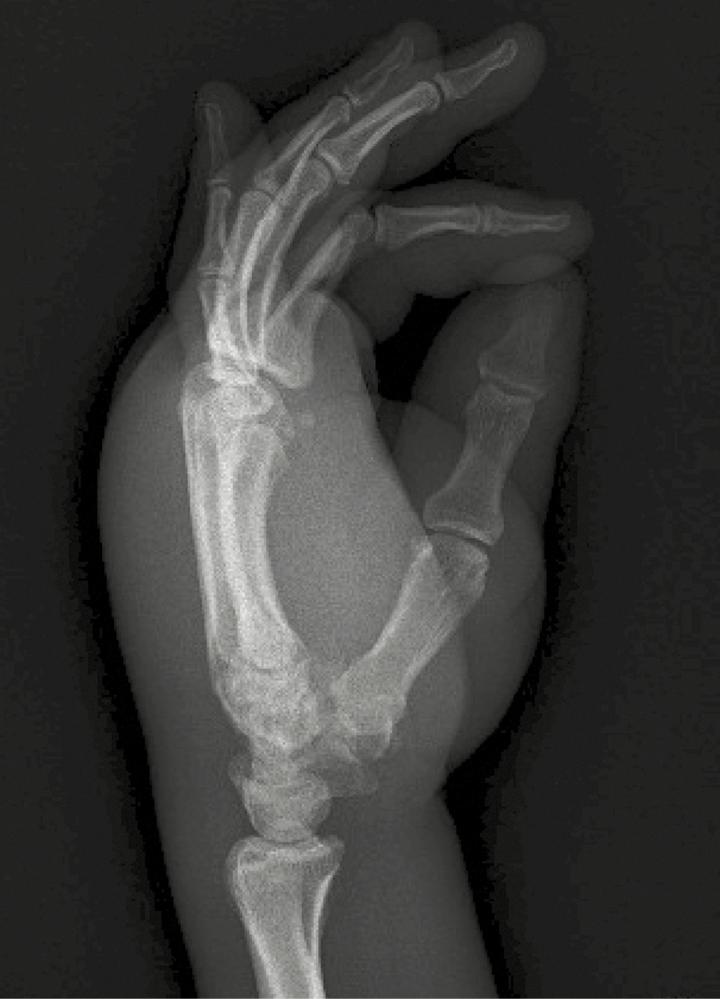

Disabling Dactylitis and Tenosynovitis Due to in a Patient With Human Immunodeficiency Virus/Acquired Immune Deficiency Syndrome.

https://cdn.ncbi.nlm.nih.gov/pmc/blobs/d0a0/5610725/25e07ae93557/ofx16501.jpg